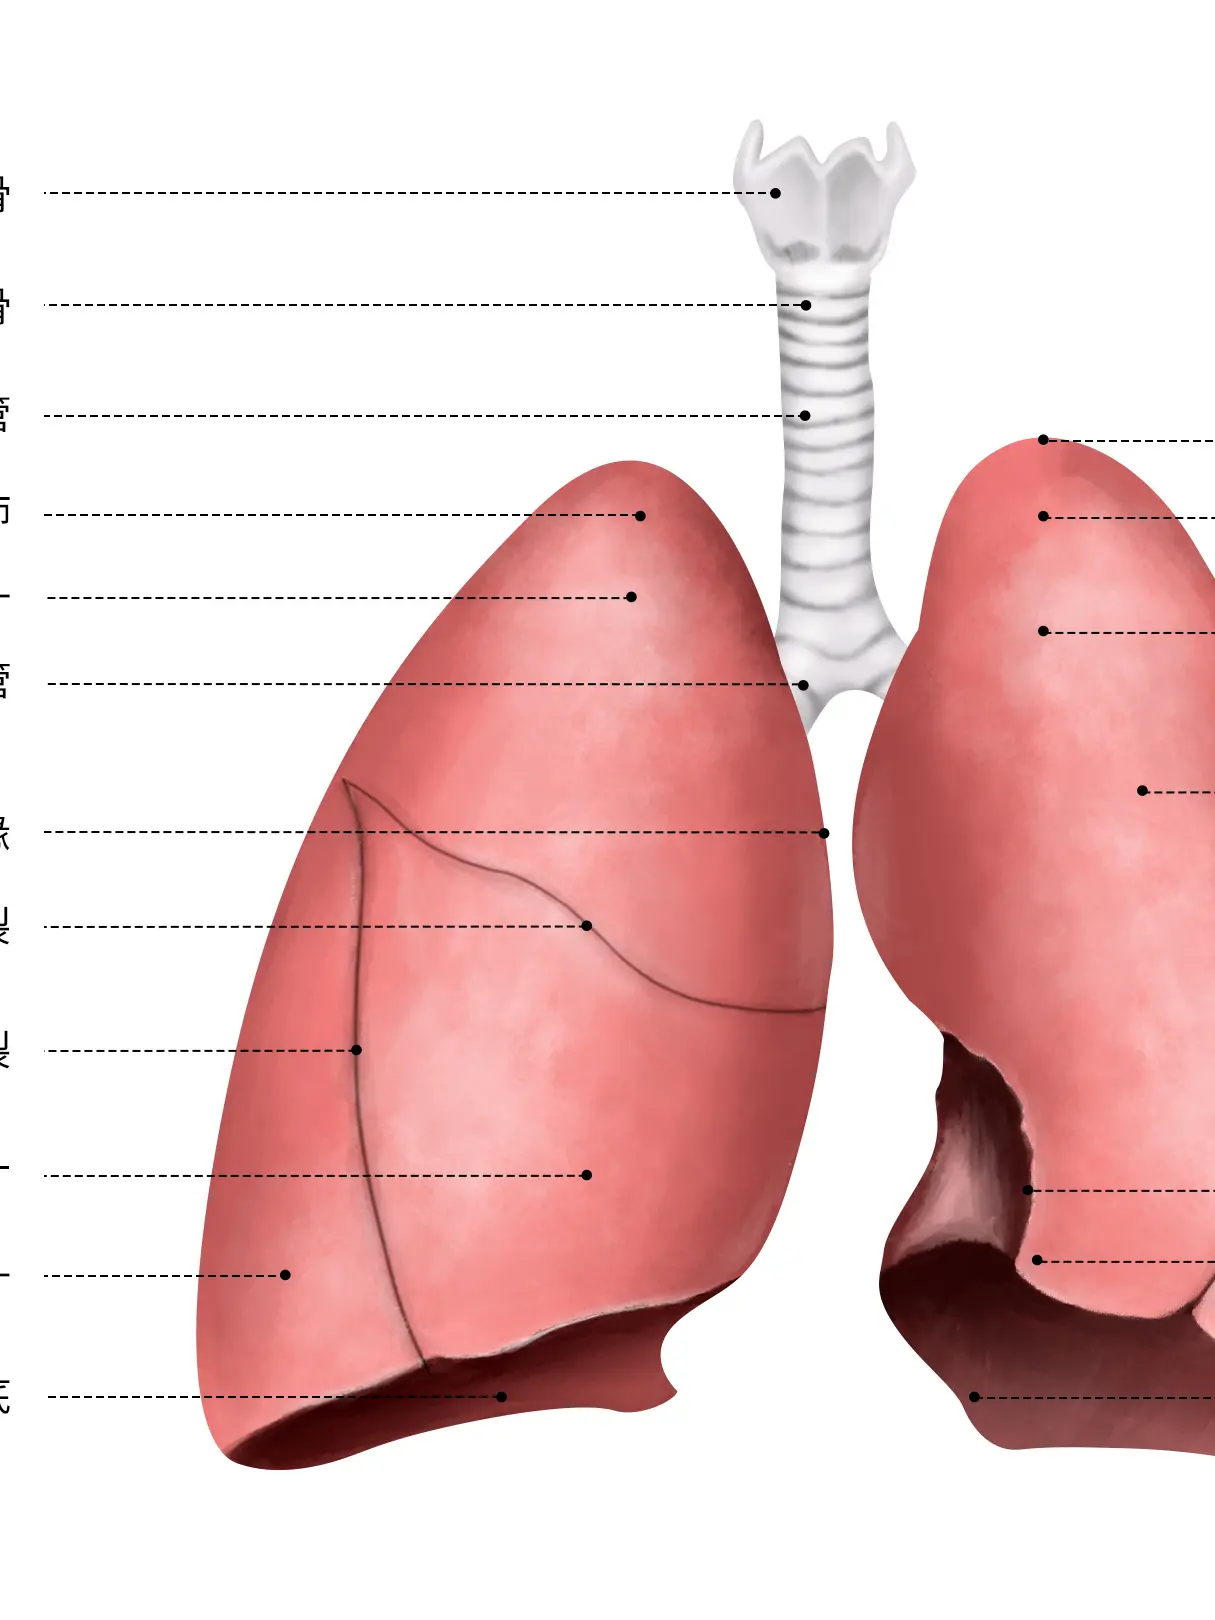

人體身上的器官科普,可以更好的了解自身的身體情況...

人體身上的器官科普,可以更好的了解自身的身體情況...